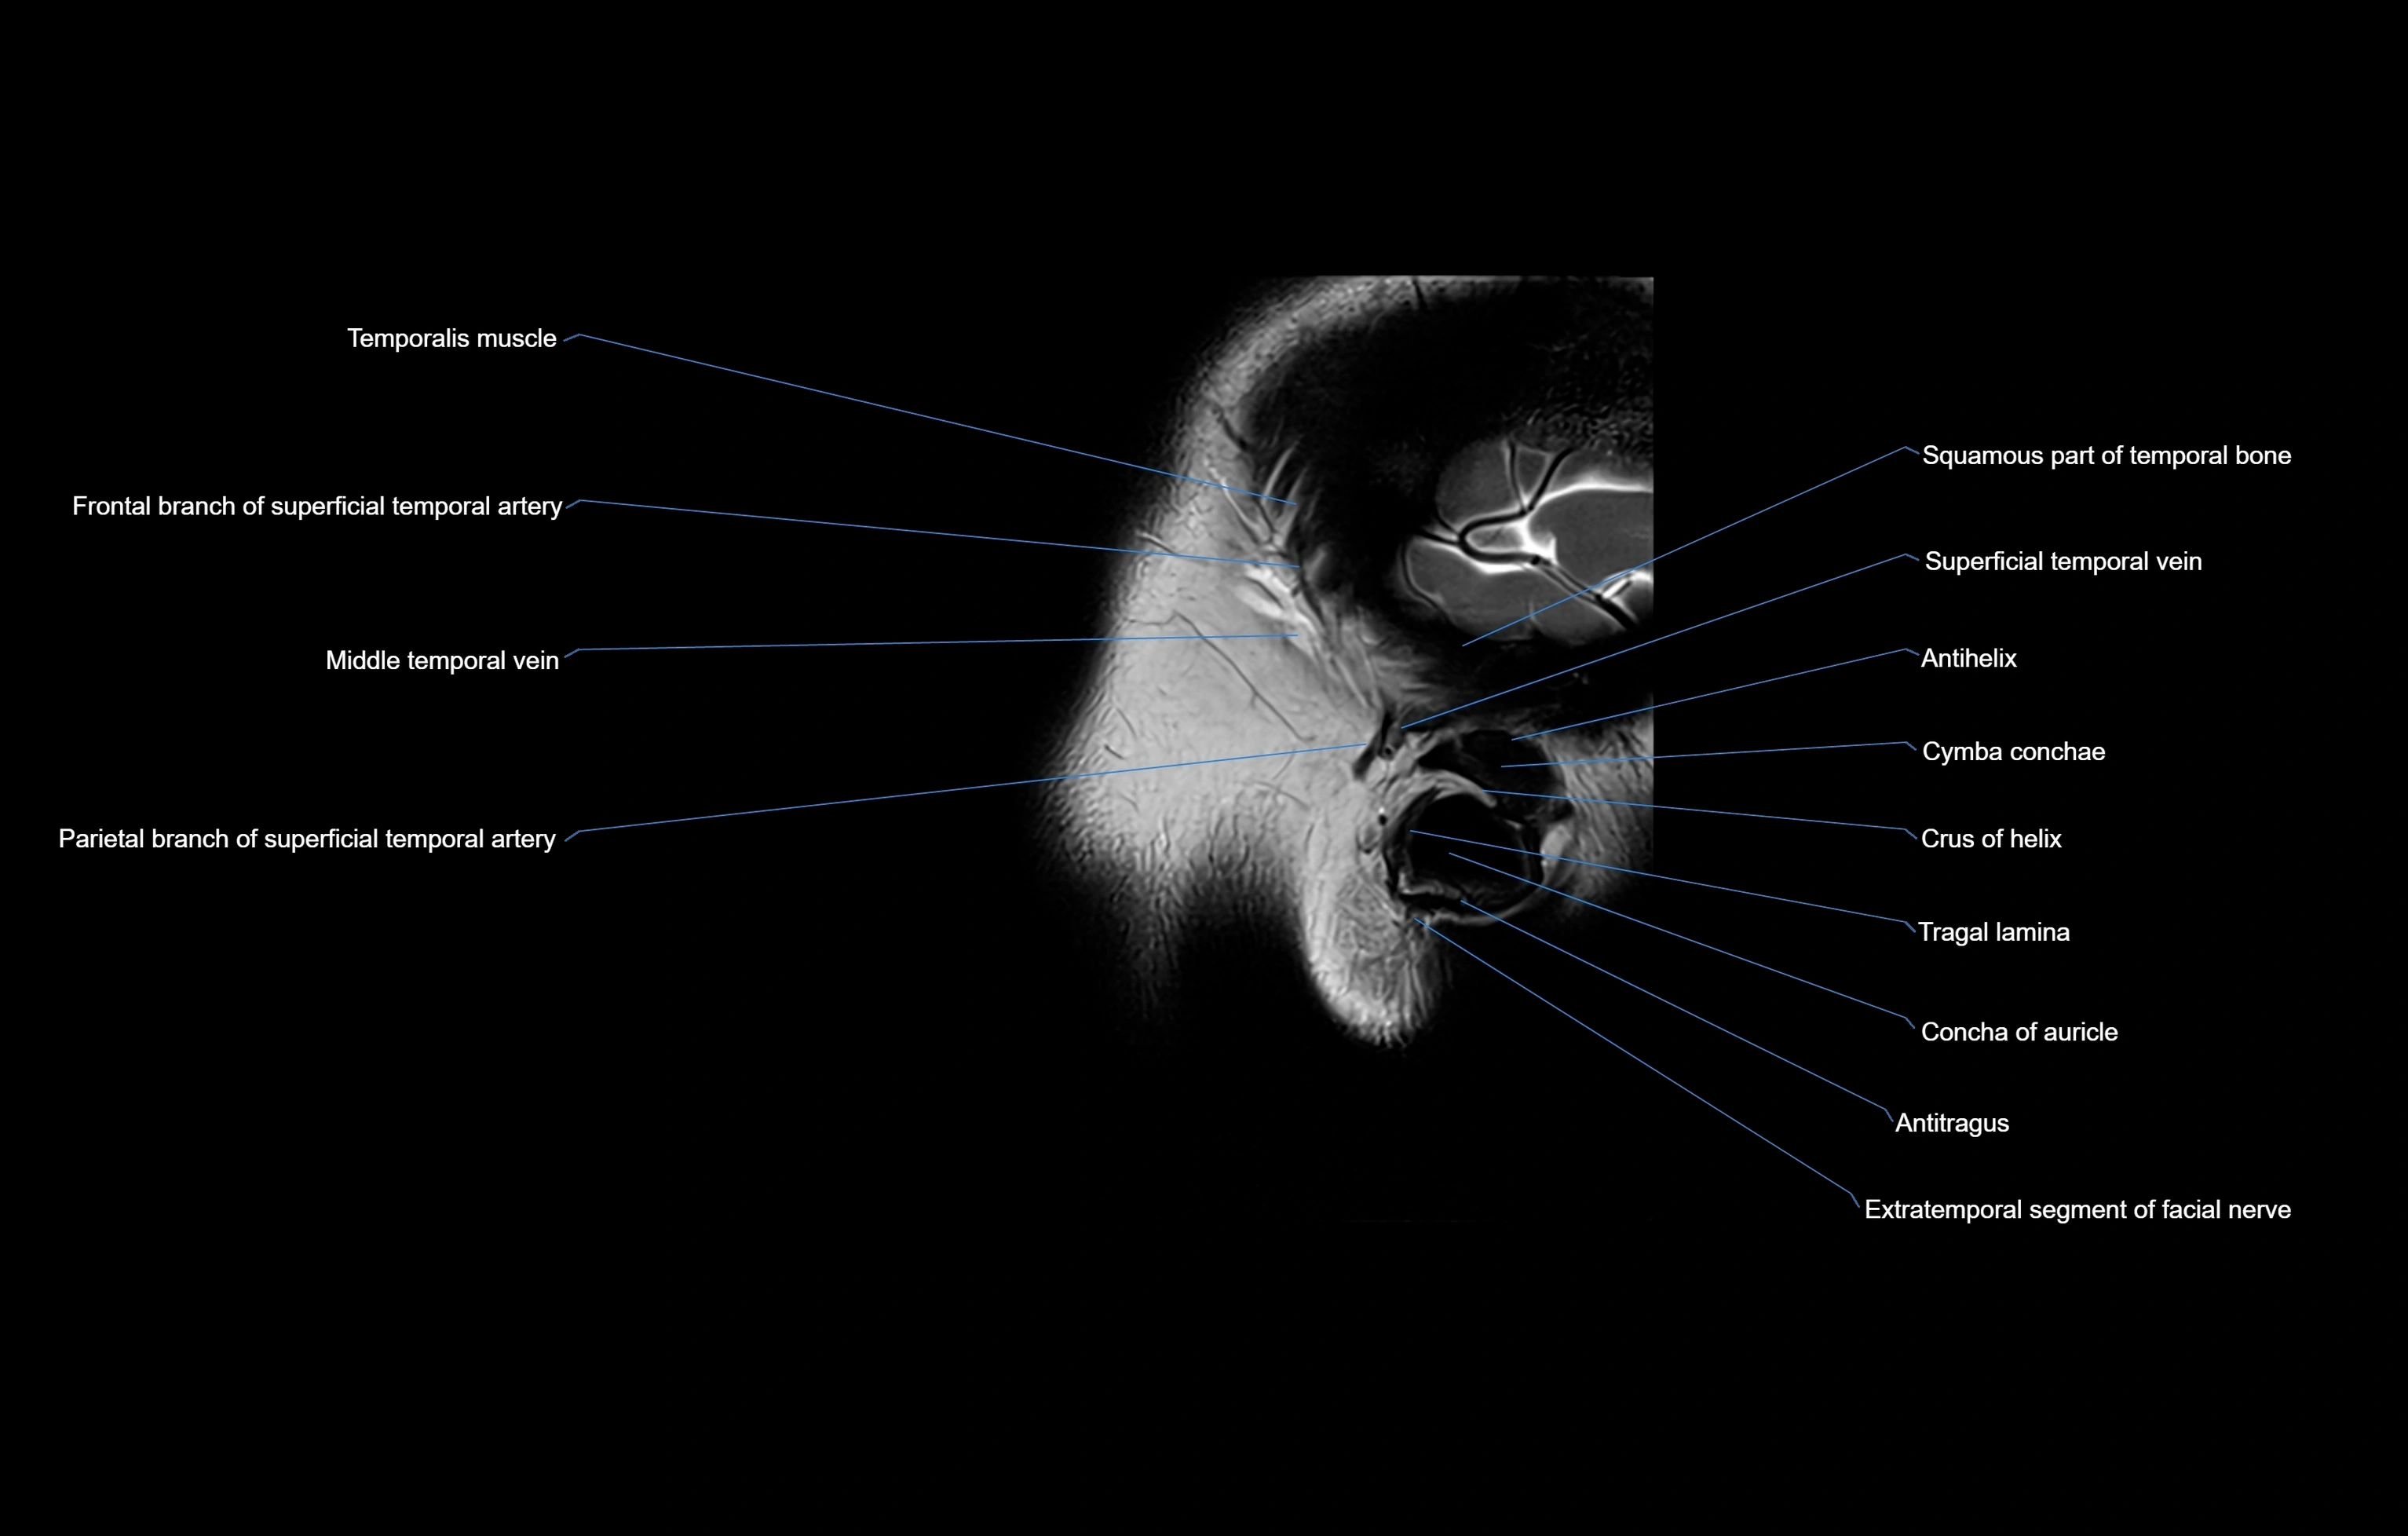

- Auricle (Pinna)

- Crus helix of ear

- Squamous part of temporal bone

- Superficial temporal vein